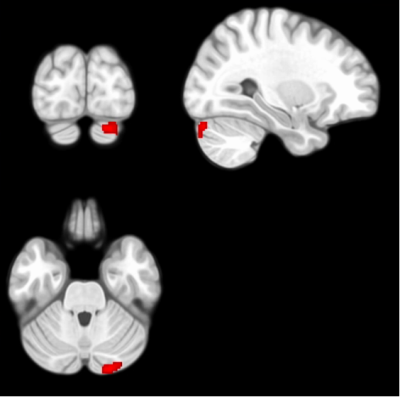

Compared with HCs, patient with CI showed increased fALFF in left cerebellum crus 1 (Figure 1). The seed-based FC analysis showed that left cerebellum crus 1 showed increased FC with right cerebellum crus 1 in patients with CI than HCs (Figure 2). The fALFF and FC values were positively correlated with symptom scores measured by CISS and NPC, and negatively correlated with horizontal phoria at near (PAN) and PFV (Tables 1 and 2).

Figure 1. The present study showed increased fALFF in the left cerebellum crus 1 of CI patients than HCs. P < 0.05, p-FWE corrected.